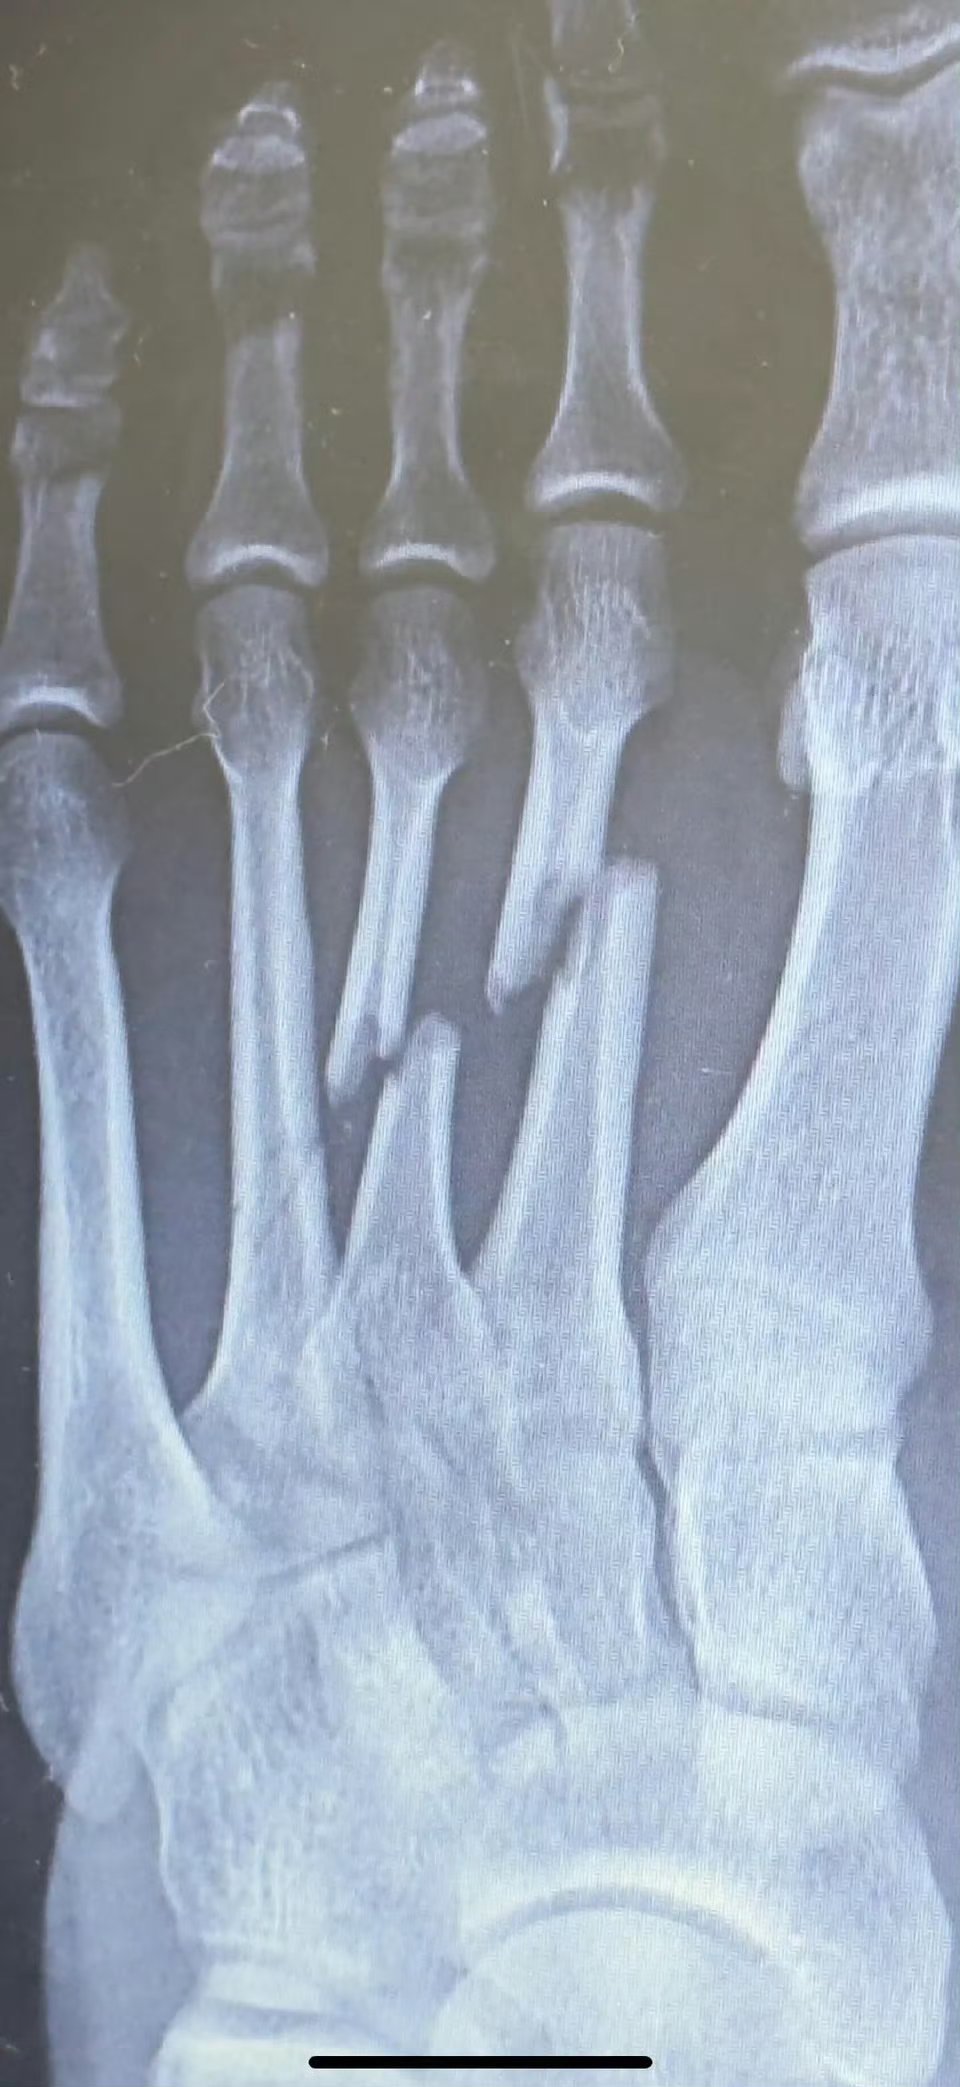

网友:脚砸伤了,没管!一年后自愈了……

你这都畸形愈合了好不好

这样的骨折,不管是不可能正常走路的。只需要复位固定不扰动(夹板,或者石膏)拐杖,护理3个月即可。

错位愈合,我有个脚趾也是

当初没拿木条固定好,还是歪了点

对位这么差也能长好属于奇迹了

畸形愈合

这个不是很严重的,我见过5根全折而且错位的,因为经济困难没有处理,就那样自己愈合了,除了外观不好看没有遗留其他毛病。其实仔细想想,脚上骨头骨折落毛病的几率不大,参考以前缠足的小脚老太太

没矫正,骨头增生了,畸形了吧

要不是我同一位置骨折我就信了,这叫跖骨,我当时是断了一根,而且还没有完全断开,根本下不了地,打石膏瘸了大半年才勉强走路,每隔三个月照片来看,骨痂长得相当慢,这TM都断来歪成啥样了,一年就能长好?别忽悠不懂的人好嘛[狗头]

骨头确实会自动连接起来,但是不去医院就行归位处理,断口会错位连接,造成畸形,